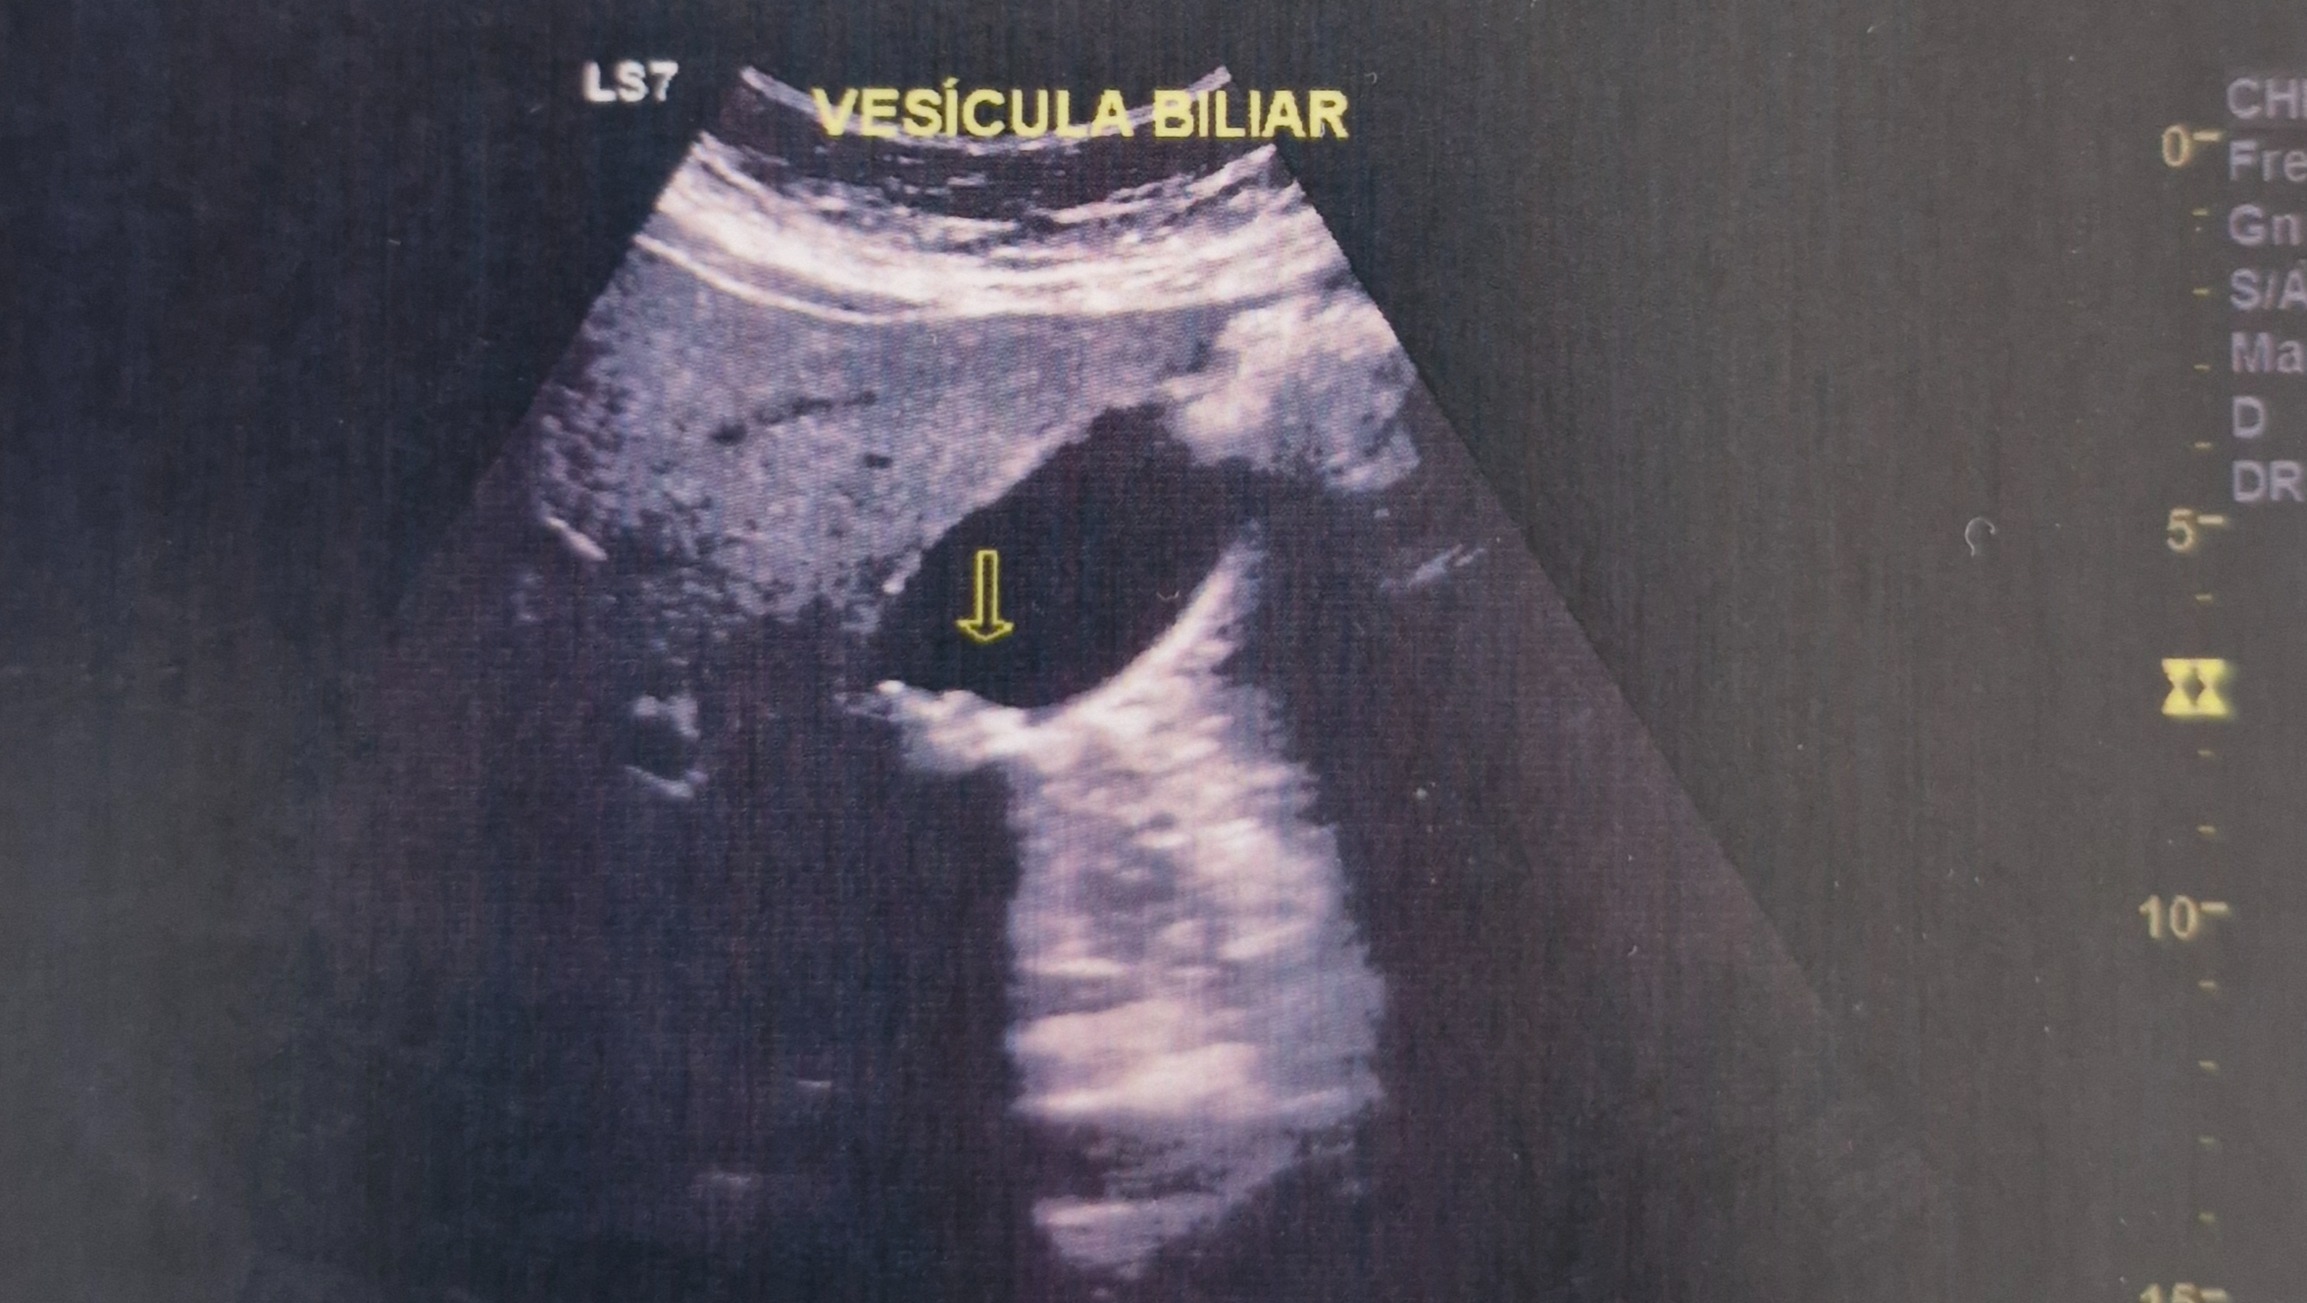

Hola, hace un mes chantel presento mucho dolor en la boca del estomago y esta semana decidimos ir al doctor por lo cual nos envio a hacer estudios en donde aparecieron 7 piedras en la vesicula por lo que se necesita una cirujia lapararoscopia por lo cual estamos pidiendo de tu apoyo de los gastos de la cirujia. muchas gracias bendiciones

Hello, a month ago Chantel had a lot of pain her stomach and this week we decided to go to the doctor. The ultrasound showed 7 stones in her gallbladder. So the laparoscopic surgery is needed and this has been scheduled for Monday the 3rd of March. The surgery costs are 40,000 pesos and we just dont have the funds for this and so this is the reason we have started this Gofundme account asking for support to cover the surgery costs. Chantel has peace and knows the Lord is with her and that He can provide for more than what we can ask for. Thank you very much, blessings.